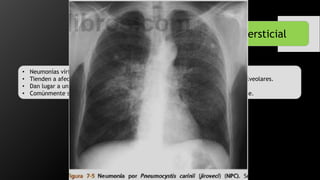

Neumonía Intersticial

• Neumonías víricas y micóticas.

• Tienden a afectar las paredes de las vías respiratorias así como de los tabiques alveolares.

• Dan lugar a un patrón reticular fino en los pulmones en rx.

• Comúnmente se diseminan a todo el pulmón con aspecto parcheado o confluyente.